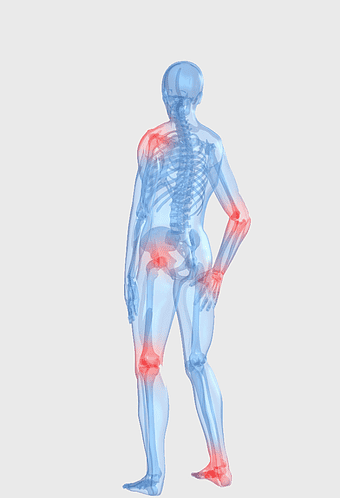

knee pain illustration, osteoarthritis joint pain, medical pain management, violet medical, skeletal joint health, chronic pain therapy, human anatomy injury -

rheumatoid arthritis illustration, chronic pain therapy, joint replacement surgery, blue violet human skeleton, skeletal anatomy diagram, arthritis pain relief methods, orthopedic health visual aids -

arthritis pain symptoms, rheumatoid arthritis illustration, joint pain areas, human body anatomy, skeletal health issues, medical visualization, chronic joint discomfort -